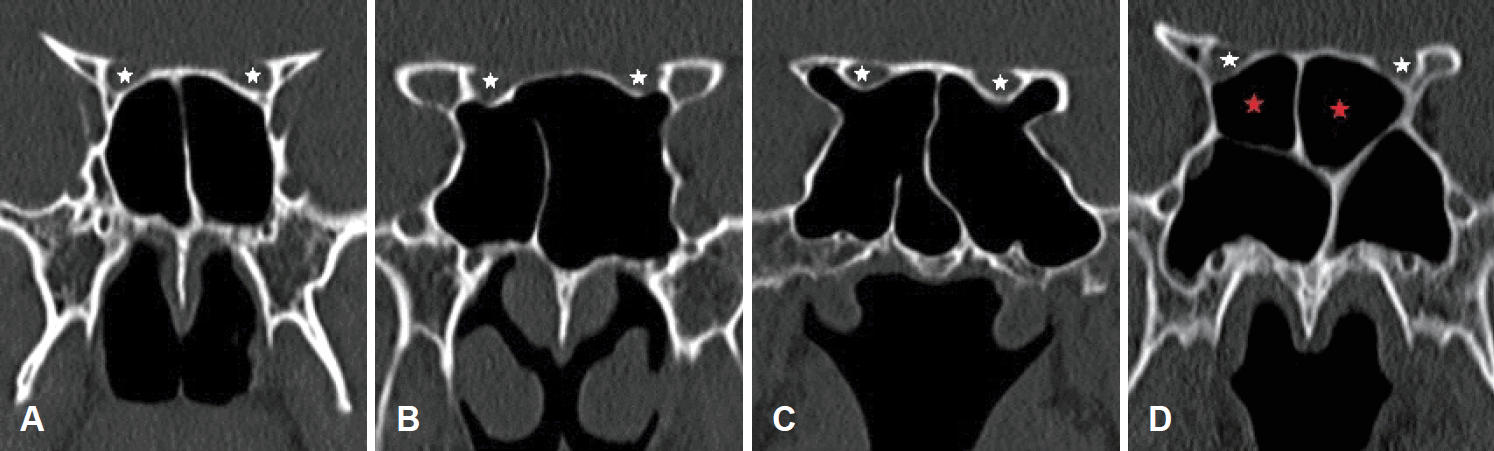

We investigated superior turbinate pneumatization (STP), middle turbinate pneumatization (MTP), agger nasi cell (ANC), infraorbital cell (IOC), optic nerve (ON) type, and vidian nerve (VN) type. We categorized ON canals into four types using the classification system by Itagi, et al. [7] (Fig. 2). Type I canal is superolateral to the SS and does not indent on the sinus wall, as seen on the coronal CT planes. Type II canal is indented on the SS contour and the indented portion is less than 50% of the nerve circumference. Type III canal traverses through the SS and coronal sections showing more than 50% projection of ON circumference into the SS. Type IV is a canal adjacent to the SS and posterior ethmoid sinuses/Onodi cell. Configurations of the VN were classified into three types (Fig. 3). Type I is considered when the VN canal completely protrudes into the SS; type II, when the canal partially protrudes into the SS or into the floor of the SS; and type III, when the canal is completely obscured within the sphenoid corpus [8].

Classification of ON into the four types on coronal CT. Type I (A), type II (B), type III (C), type IV (D) (white star: ON, red star: Onodi cell). ON: optic nerve.